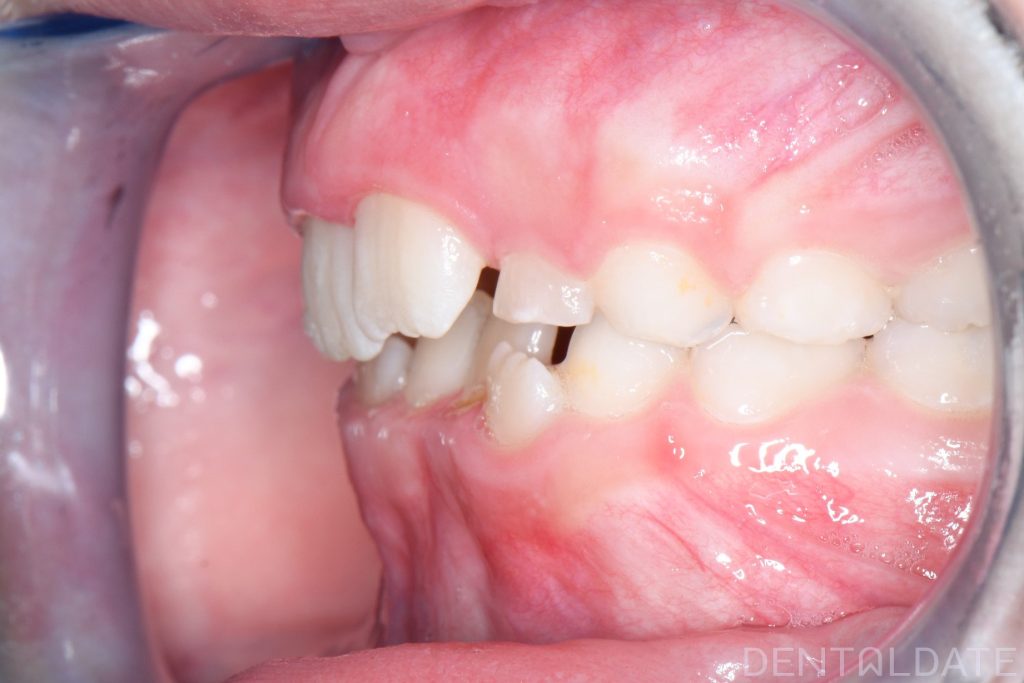

Parents sought an orthodontic consultation due to concerns about the aesthetics of their child’s smile.

To achieve harmony between function and aesthetics, a Haas appliance was used, followed by a myofunctional appliance.